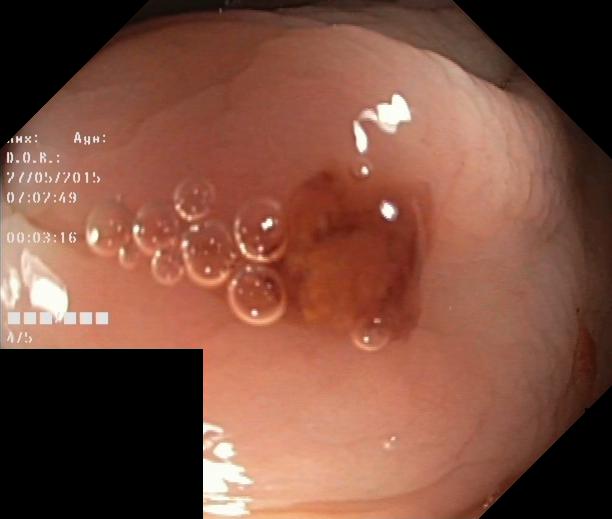

We have used a polyp dataset published with HyperKvasir dataset [51], which consists of polyp findings extracted from endoscopy examinations. HyperKvasir contains polyp images with corresponding segmentation masks annotated by medical experts. We use only this polyp dataset as a case study because of the time and resource-consuming training process of the SinGAN-Seg pipeline. However, the SinGAN-Seg model and pipeline can be used for any segmentation dataset.

A few sample images and the corresponding masks of the polyp dataset in HyperKvasir are shown in Fig 2. The polyp images are RGB images. The masks of the polyp images are single-channel images with white () for true pixels, which represent polyp regions, and black () for false pixels, which represent clean colon or background regions. In this dataset, there are different sizes of polyps. The distribution of polyp sizes as a percentage of the full image size is presented in the histogram plot in Fig 3, and we can observe that there are more relatively small polyps compared to larger polyps. Additionally, a subset of this dataset was used to prove that the performance of segmentation models trained with small datasets can be improved using our SinGAN-Seg pipeline, and the whole dataset was used to show the effect of using SinGAN-Seg generated synthetic images instead of a large dataset which has enough data to train segmentation models. In this regard, this dataset was used for two purposes: